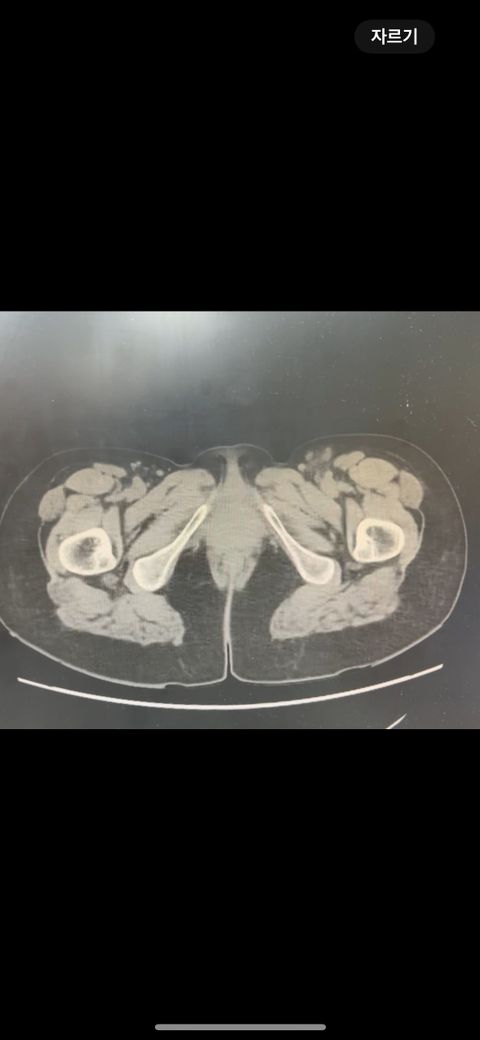

복부 ct 영상 판독부탁드립니다.!

결과는 3일 후 볼 예정인데 우선 영상만 받은 상태이고 너무 궁금한데 영상가지고 판독을 못해서요,,

이 사진가지고 확인할 수 있을까요 ?